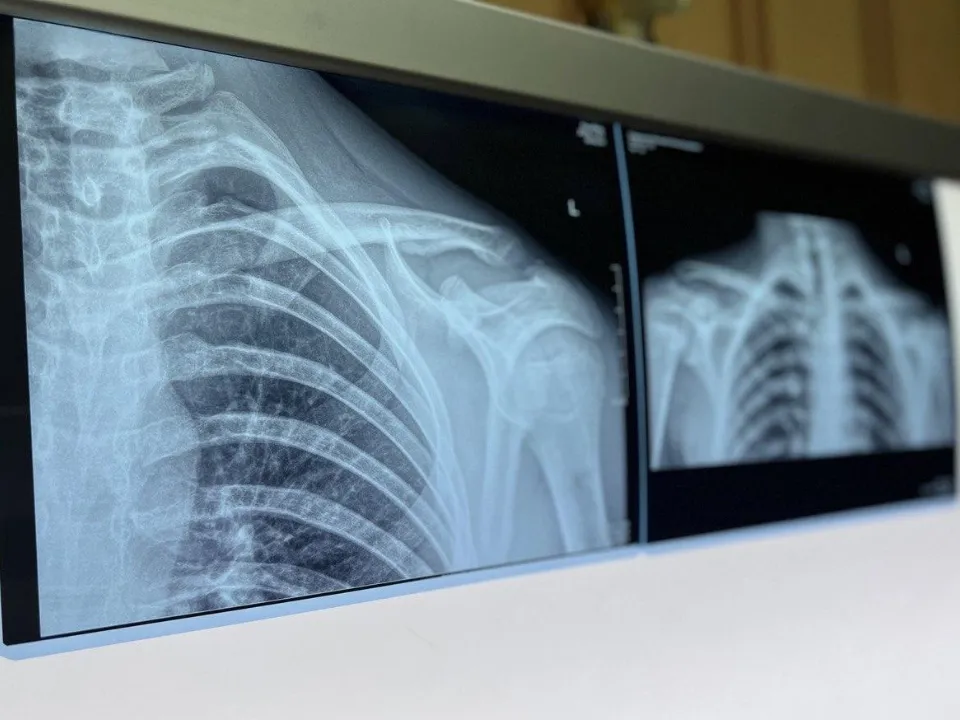

Ранее REGIONS сообщал, что медучреждения Подмосковья с начала года получили 38 современных рентген-аппаратов.